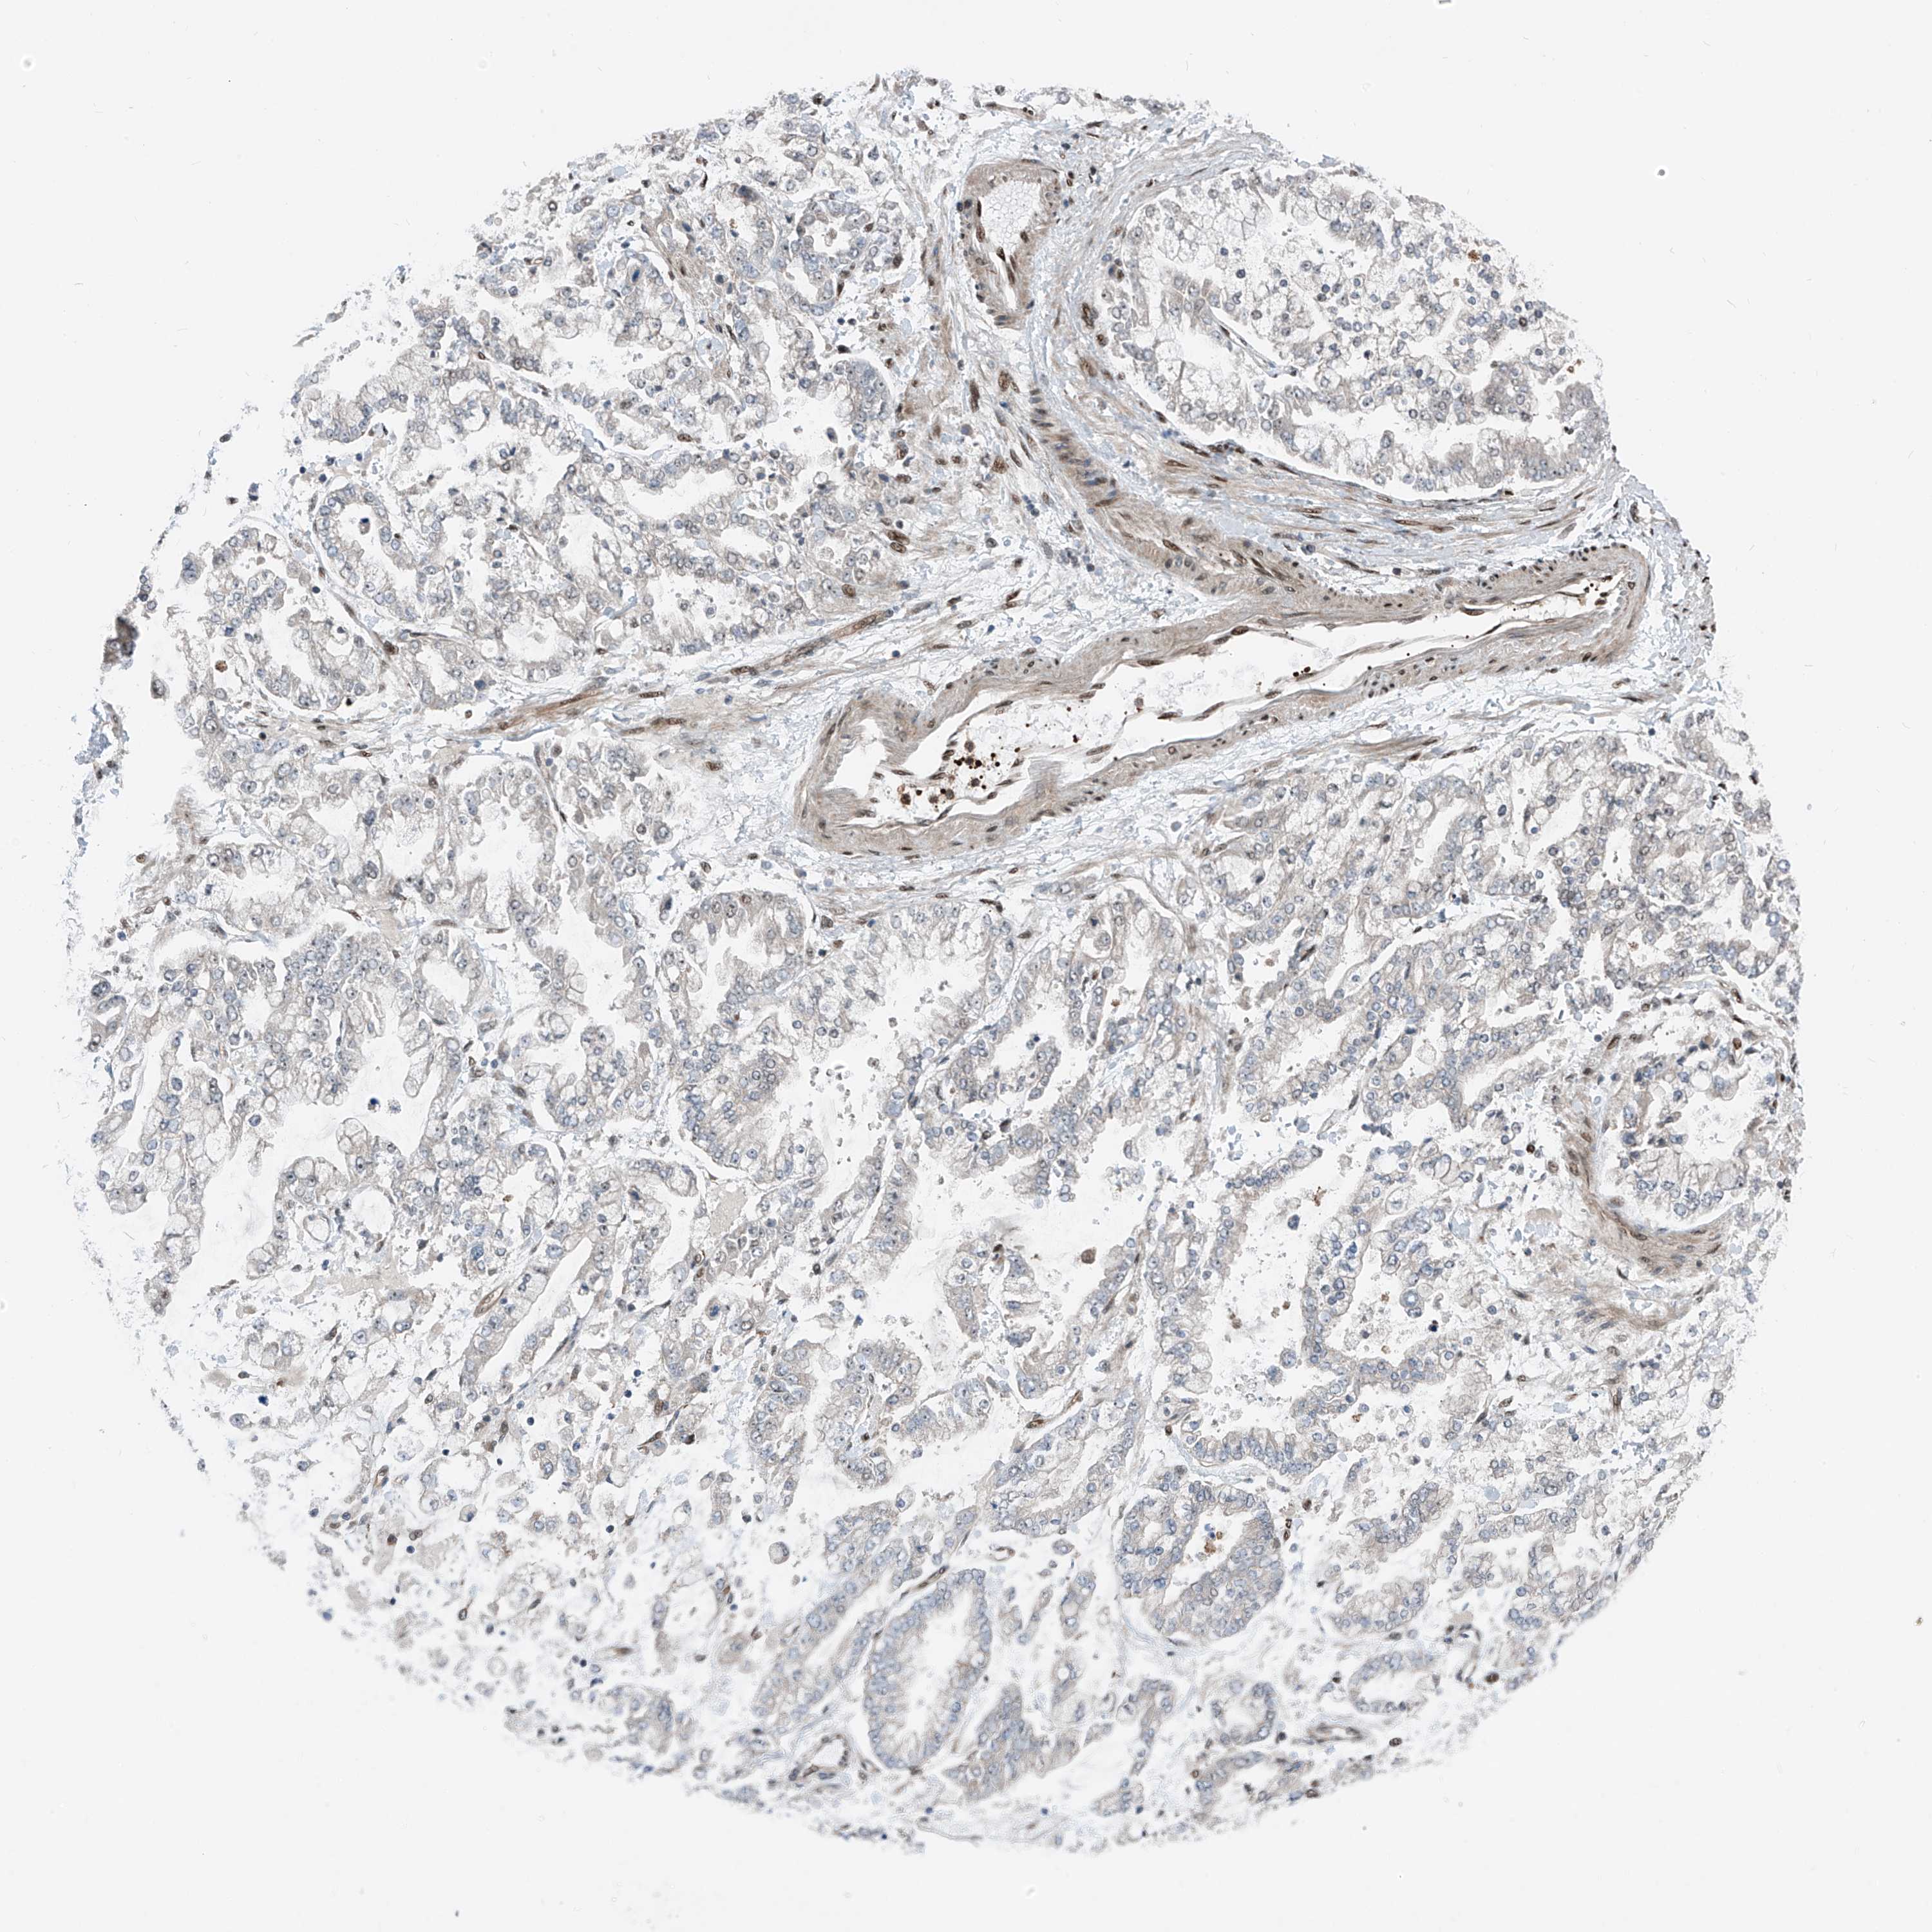

STOMACH CANCER - Protein expressioni

A mouse-over function shows sample information and annotation data. Click on an image to view it in a full screen mode. Samples can be filtered based on level of antibody staining by selecting one or several of the following categories: high, medium, low and not detected. The assay and annotation is described here.

Note that samples used for immunohistochemistry by the Human Protein Atlas do not correspond to samples in the TCGA dataset.

Antibody stainingi

Antibody staining in the annotated cell types in the current human tissue is reported as not detected, low, medium, or high, based on conventional immunohistochemistry profiling in selected tissues. This score is based on the combination of the staining intensity and fraction of stained cells.

Each image is clickable and will lead to virtual microscopy that enables deeper exploration of all samples and also displays staining intensity scores, fraction scores and subcellular localization as well as patient and tissue information for each sample.

Antibody HPA034749

Staining

High

Medium

Low

Not detected

Intensity

Strong

Moderate

Weak

Negative

Quantity

>75%

75%-25%

<25%

None

Location

Nuclear

Cytoplasmic/membranous

Cytoplasmic/membranous,nuclear

Adenocarcinoma, NOS